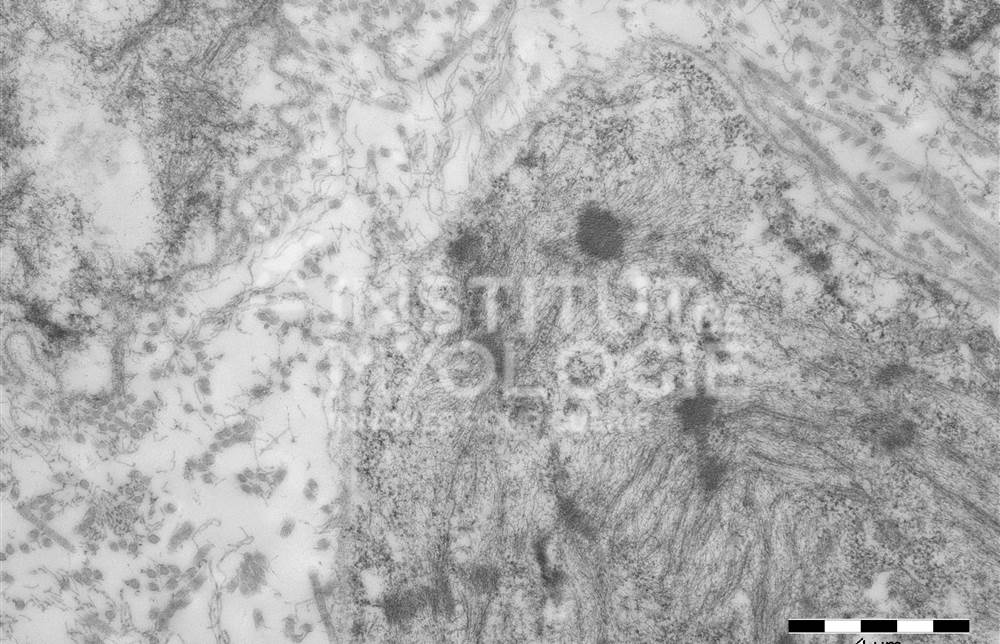

Welcome to the Muscle Atlas, the first database of muscle images designed to facilitate research, diagnosis and knowledge in the field of neuromuscular pathologies. Our vast collection includes more than 6,416 images of muscle biopsies from patients with various diseases and animal models, which may or may not be undergoing treatment. Each image is characterised according to the specific condition and corresponding stage of the disease.